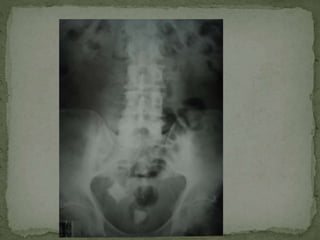

 CXR CHEST/ ABDOMIN

 Simple Investigations: Bloods tests (FBC, U&E, LFT, amylase, clotting, CRP, G&S/ ABG)  Urine dipstick  Pregnancy test (all women of child bearing age with lower abdominal pain)  CXR CHEST/ ABDOMIN  ECG  More ADVANCE investigations:  Contrast studies  Endoscopy (OGD/colonoscopy/ERCP)  CT  MRI